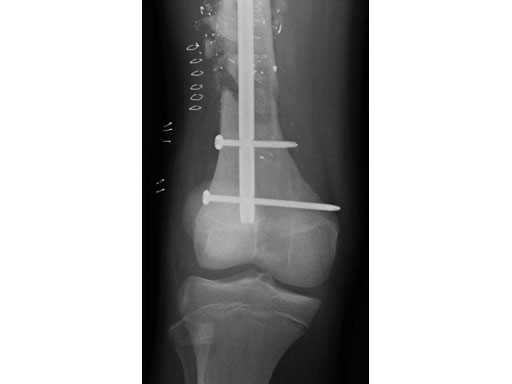

Fig 3cd Lateral x-rays 6 months postoperatively.